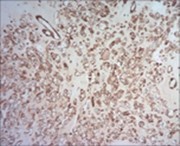

Figure 8.Parachordoma demonstrating immune reactivity to vimentin 16.